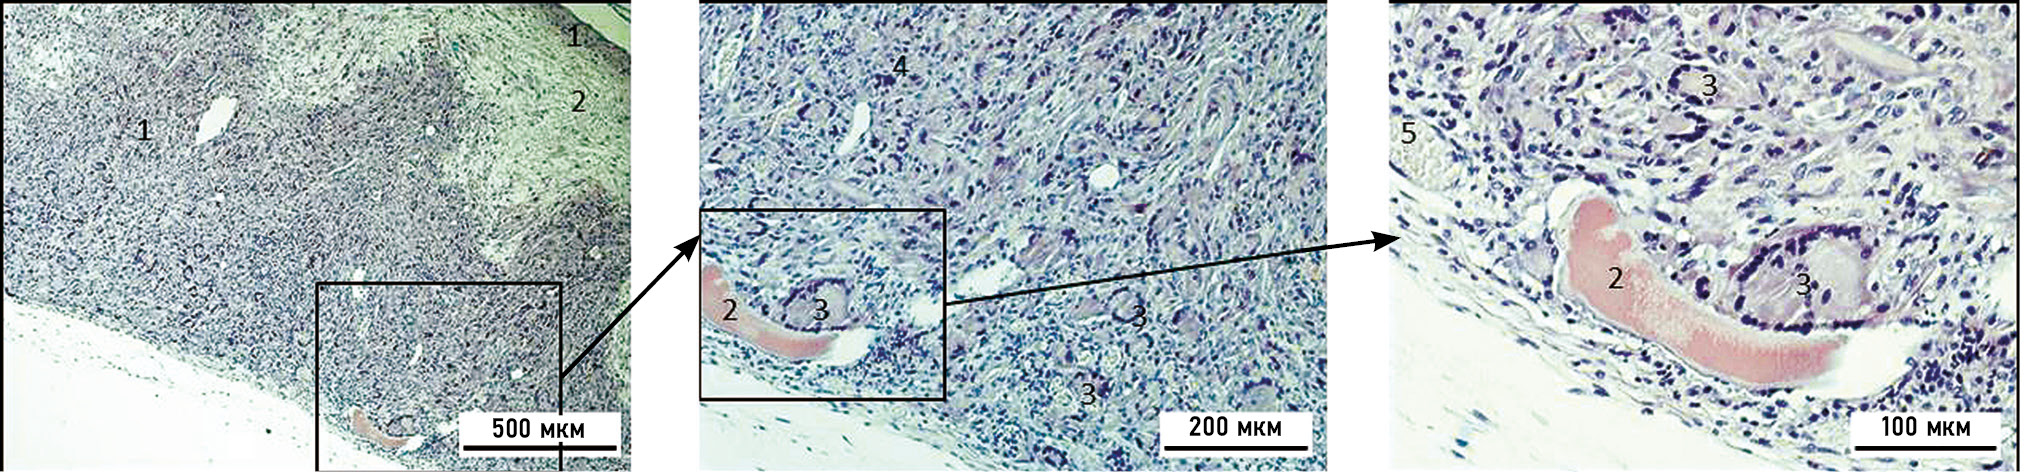

На гистопрепарате подкожной имплантации бесколлагеновой мембраны через 2 нед по периметру вокруг неё визуализируется формирование гранулёмы по типу реакции на инородное тело, с чёткими границами. Наблюдается появление единичных гигантских многоядерных клеток инородных тел и клеток Пирогова–Лангханса по поверхности мембраны. Материал мембраны однородной структуры равномерно разрыхлён (рис. 3).

Рис. 3. Микрофотография бесколлагеновой мембраны через 2 нед после её подкожной имплантации, окраска — азур-эозин: 1 — гранулёма инородного тела; 2 — бесколлагеновая мембрана; 3 — кровеносные сосуды; 4 — гигантские клетки инородных тел; 5 — гигантские клетки Пирогова–Лангханса.

Fig. 3. Microphotograph of collagen-free membrane after 2 weeks its subdermal implantation, staining — azure-eosin: 1 — foreign body granuloma; 2 — collagen-free membrane; 3 — blood vessels; 4 — foreign body giant cells; 5 — Pirogov–Langhans giant cells.